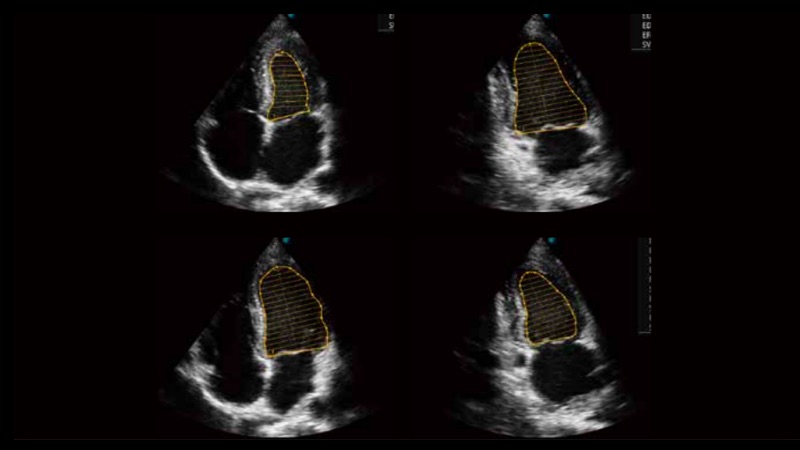

自動識別收縮和舒張末期心肌內(nèi)膜,自動計算射血分數(shù)EF值。